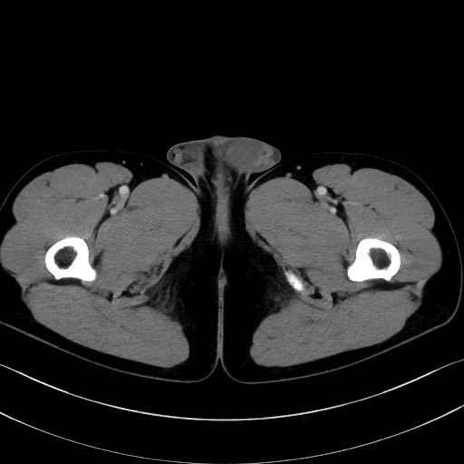

2. 腸腰筋群と骨盤底筋

大腰筋 (Psoas major)

腸骨筋 (Iliacus)